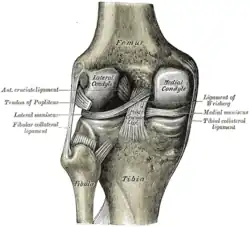

Il s'articule en haut avec le fémur au niveau de l'articulation fémoro-tibiale. En bas il s'articule avec le talus pour former avec la contribution de la fibula l'articulation talo-crurale. Il est uni à la fibula par deux arthrodies : les articulations tibio-fibulaires proximale et distale.

Sa face supérieure horizontale constitue le plateau tibial. Il est constitué de deux tubérosités formant les condyles du tibia : un latéral et un médial. Les deux sont recouverts de cartilage hyalin qui constituent les surfaces articulaires supérieures du tibia (la surface articulaire du condyle médial du tibia et la surface articulaire supérieure du condyle latéral du tibia). Elles sont séparées par la surface intercondylaire.

Le condyle latéral est large et convexe vers le haut alors que le condyle médial est étroit et concave.

Les deux condyles s'articulent respectivement avec les condyles latéral et médial du fémur pour constituer l'articulation du genou.

Insertions ligamentaires

- Sur l'éminence intercondylaire s'insèrent les quatre freins méniscaux (antéro-latéral, antéro-médial, postéro-latéral et postéro-médial) , ils permettent de fixer les ménisques de l'articulation du genou.

- Sur les aires intercondylaires antérieure et postérieure on retrouve respectivement le ligament croisé antérieur et le ligament croisé postérieur. Ils empêchent respectivement le tiroir antérieur et le tiroir postérieur.

- Le ligament transverse se situe sur la face antérieure du genou et relie la face antérieure des deux ménisques. Il possède une troisième insertion sur la partie antérieure du plateau tibial.

- Pour renforcer la capsule articulaire du genou on retrouve entre autres le ligament collatéral tibial qui s'insère sur la face médiale de l'épiphyse distale du fémur et sur la face médiale de l'épiphyse proximale. Ce ligament est constitué d'un chef profond qui est lié au ménisque médial et un chef plus superficiel.